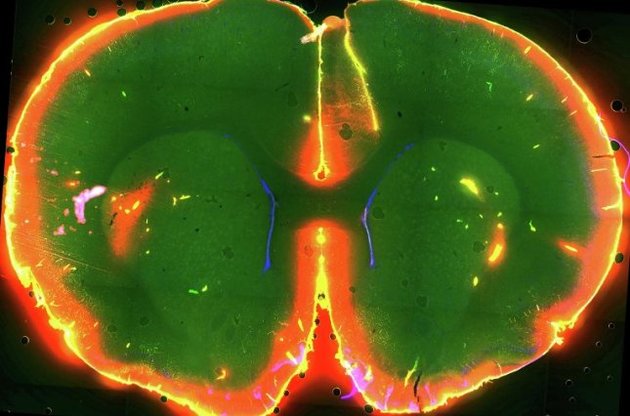

Ранее группа Недергаард открыла в головном мозге глимфатическую систему - сеть канальцев, по которым быстро циркулирует спинномозговая жидкость (ликвор) вымывающая продукты жизнедеятельности клеток.

Она и ее коллеги в эксперименте с мышами наблюдали за процессами, происходящими в живом неповрежденном мозге с помощью метода двупротонной микроскопии. Как оказалось, у спящих мышей глимфатическая система работает в 10 раз активней. За время сна мозг животных избавляется от бета-амилоида - вещества, накопление которого ведет к болезни Альцгеймера.

Во сне клетки мозга уменьшаются на 60%, облегчая ликвору перемещение между тканями. При пробуждении клетки увеличиваются, ток жидкости ограничивается. В спящем мозге менее активен гормон норадреналин, который отвечает за быструю реакцию на внешние стимулы. Ученые считают, что именно он регулирует сжатие и расширение мозговых клеток в циклах сна-бодрствования. !zn